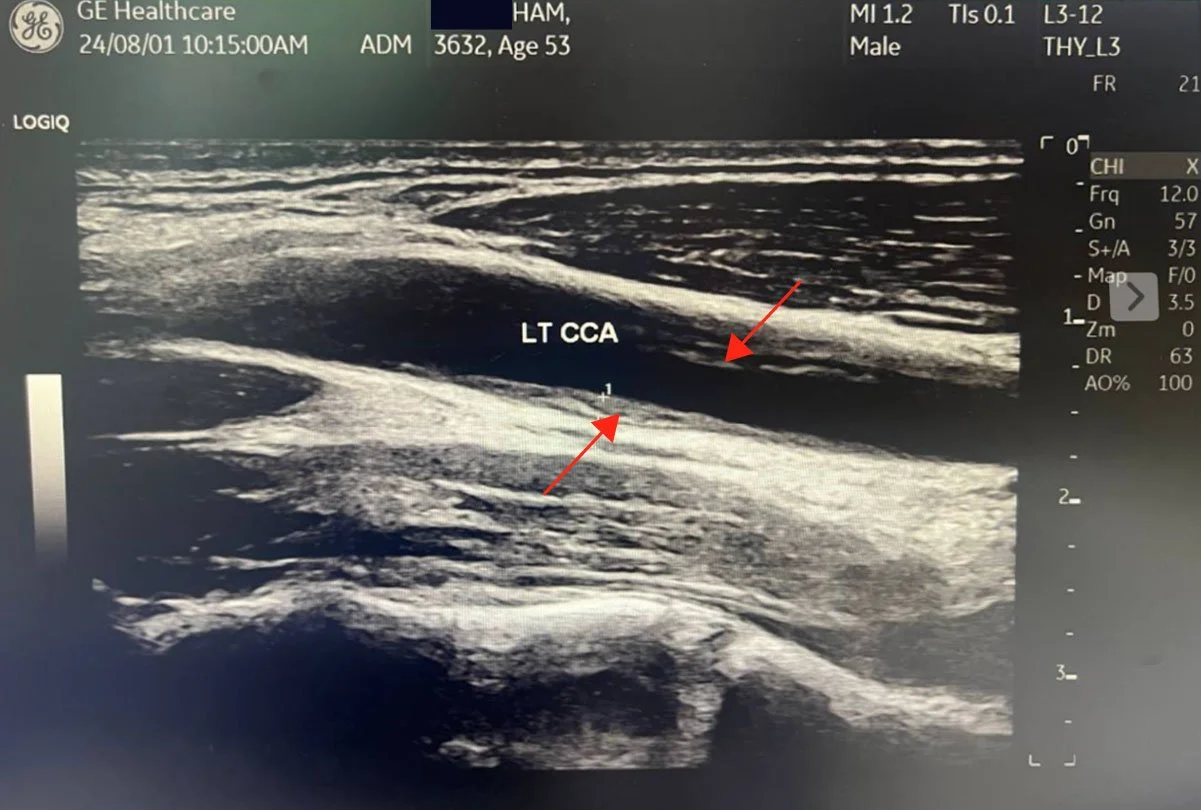

And here is what reversal looks like. My carotid plaque. Gone. Remodeled. In three months. Bilateral carotid IMT of 1.8 mm and 1.6 mm with visible plaque on both sides, dropping to 0.84 mm and 0.86 mm with no visible plaque detectable on ultrasound. My CT-FFR on a dominant D1 diagonal with 77 percent stenosis: improved from 0.75 to 0.80, crossing from ischemic into the normal range. LDL: 61, a 64 percent reduction. ApoB: 45. The word my physician friends used: Unbelievable!

Before: RT CCA . Longitudinal . Baseline

After: Plaque remodeling and reversal. B-mode ultrasound imaging of the carotid artery. Kevin Ham, MD, 2025. Three months on the CAST protocol: WFPB diet, high-intensity cycling, structured fasting, targeted supplementation.